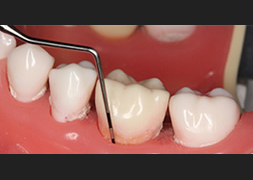

歯周病になってしまった原因と進行状況を調べます。詳しい問診、レントゲン(パノラマX線写真・全顎デンタルX線写真)、歯周ポケットの深さを測定する歯周組織検査、スタディモデル(歯型)、口腔内写真、歯周ポケットから採取したプラークをDNAレベルで検査する歯周病細菌検査、からなります。

歯周組織検査

ブラッシング指導・スケーリング

歯周病の原因となる歯周病菌を取り除くため、ブラッシング指導スケーリング(表面の歯石の除去)を行います。歯周病治療の成否を決める重要な段階ですので、歯科医師と担当歯科衛生士が、時間をかけて丁寧に行います。

再評価

セルフケアやスケーリングの成果があがり炎症がおさまったかどうか確認します。歯肉炎や初期の歯周炎であればこの段階で治癒が期待できます。